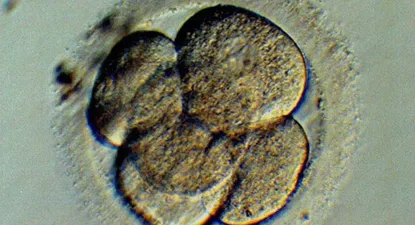

Primero se incorporarán las técnicas de baja complejidad en casi todas las instituciones